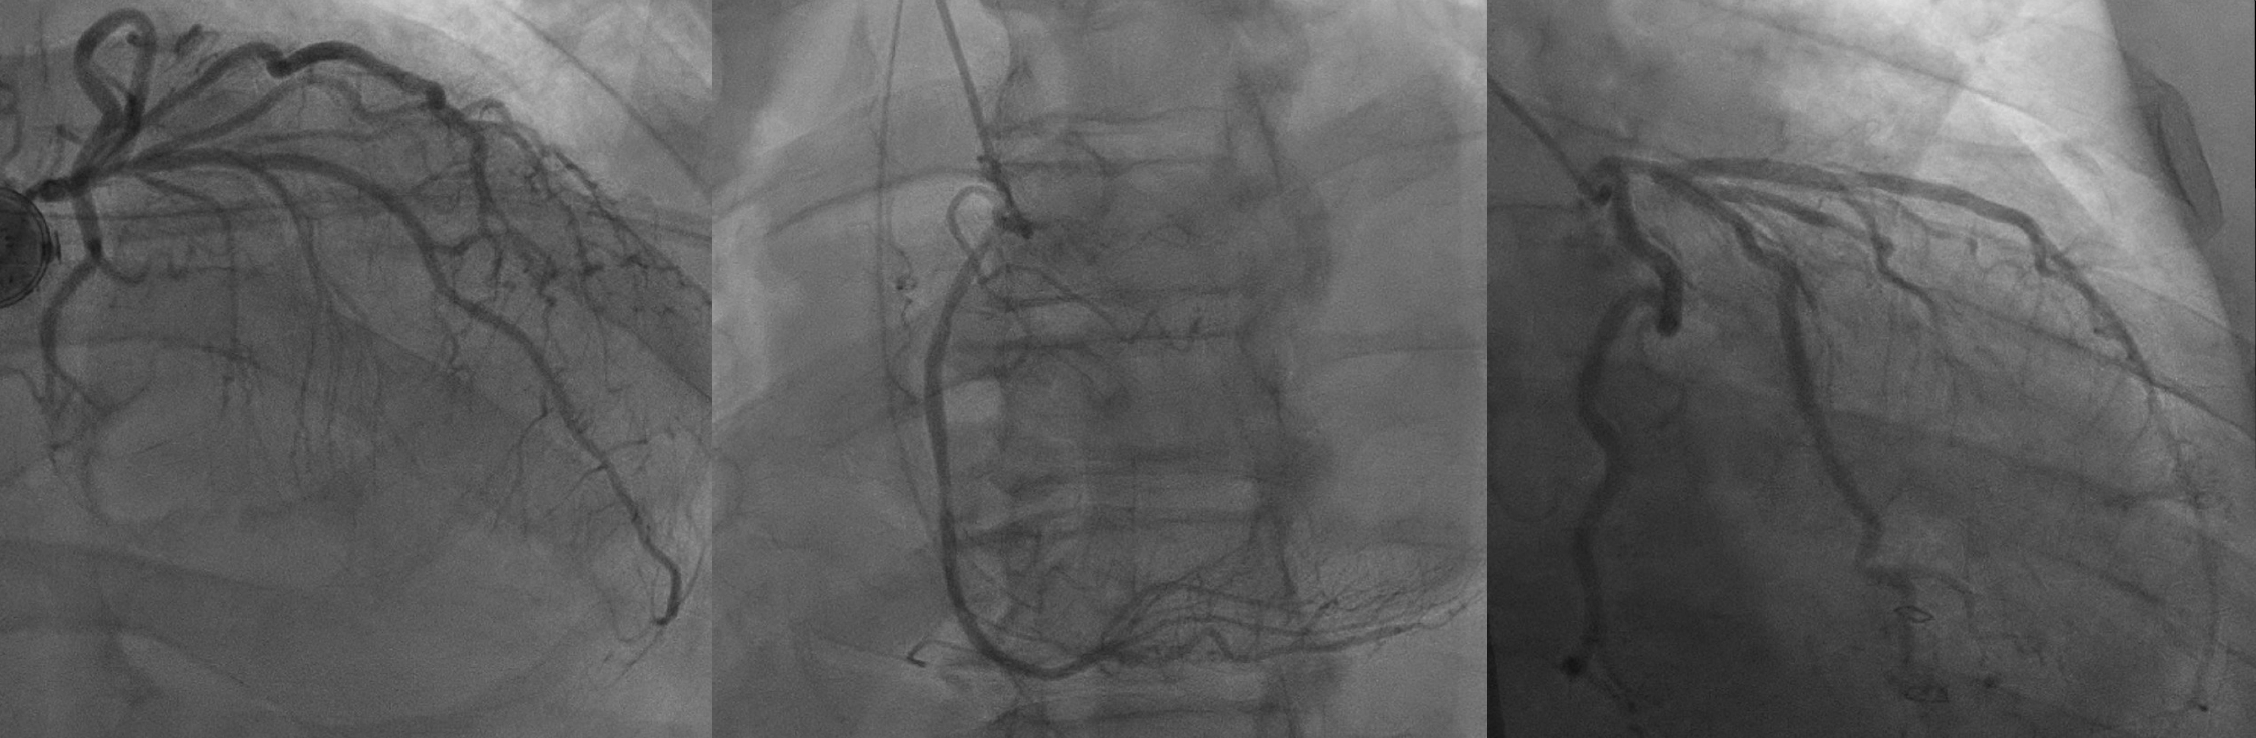

We present the case of a 68-year-old male with cirrhosis and hepatocellular carcinoma who developed multiple episodes of pulseless electrical activity (PEA) arrest following emergent abdominal surgery. The patient underwent electrocardiography, echocardiography, and coronary angiography. Clinical findings were reviewed alongside laboratory and imaging data to identify a unifying cause.

Post-arrest echocardiography demonstrated a reduced ejection fraction with anterior and apical akinesis. Coronary angiography showed no critical lesions but revealed subtle luminal irregularities in the LAD. The patient experienced multiple episodes of QRS widening, ST changes, hypotension, and PEA arrest—all transient and resolving within minutes. Electrolytes were largely normal. Coronary vasospasm was suspected based on episodic ischemic ECG changes, angiographic findings, and lack of metabolic or structural explanations. The patient was managed with intravenous nitroglycerin, later transitioned to clevidipine, with vasopressor support using norepinephrine. After initiating anti-vasospastic therapy, ischemic episodes and arrests abated. Repeat TTE redemonstrated LV concentric remodeling, hyperdynamic systolic function with recovered EF.